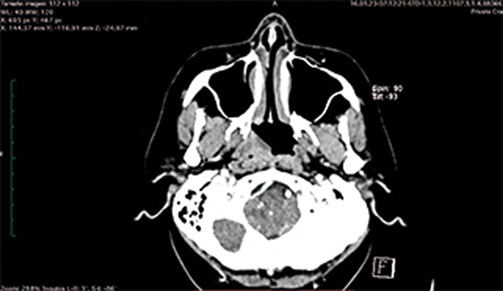

Se tomó tomografía contrastada de macizo facial, la que se apreció sin cambios evidentes, únicamente se advirtió un ligero aumento de volumen en la pared faríngea izquierda (figura 2).

Figura 2. Obsérvese dentro del circulo, zona hipodensa con aumento de volumen de pared de nasofaringe.